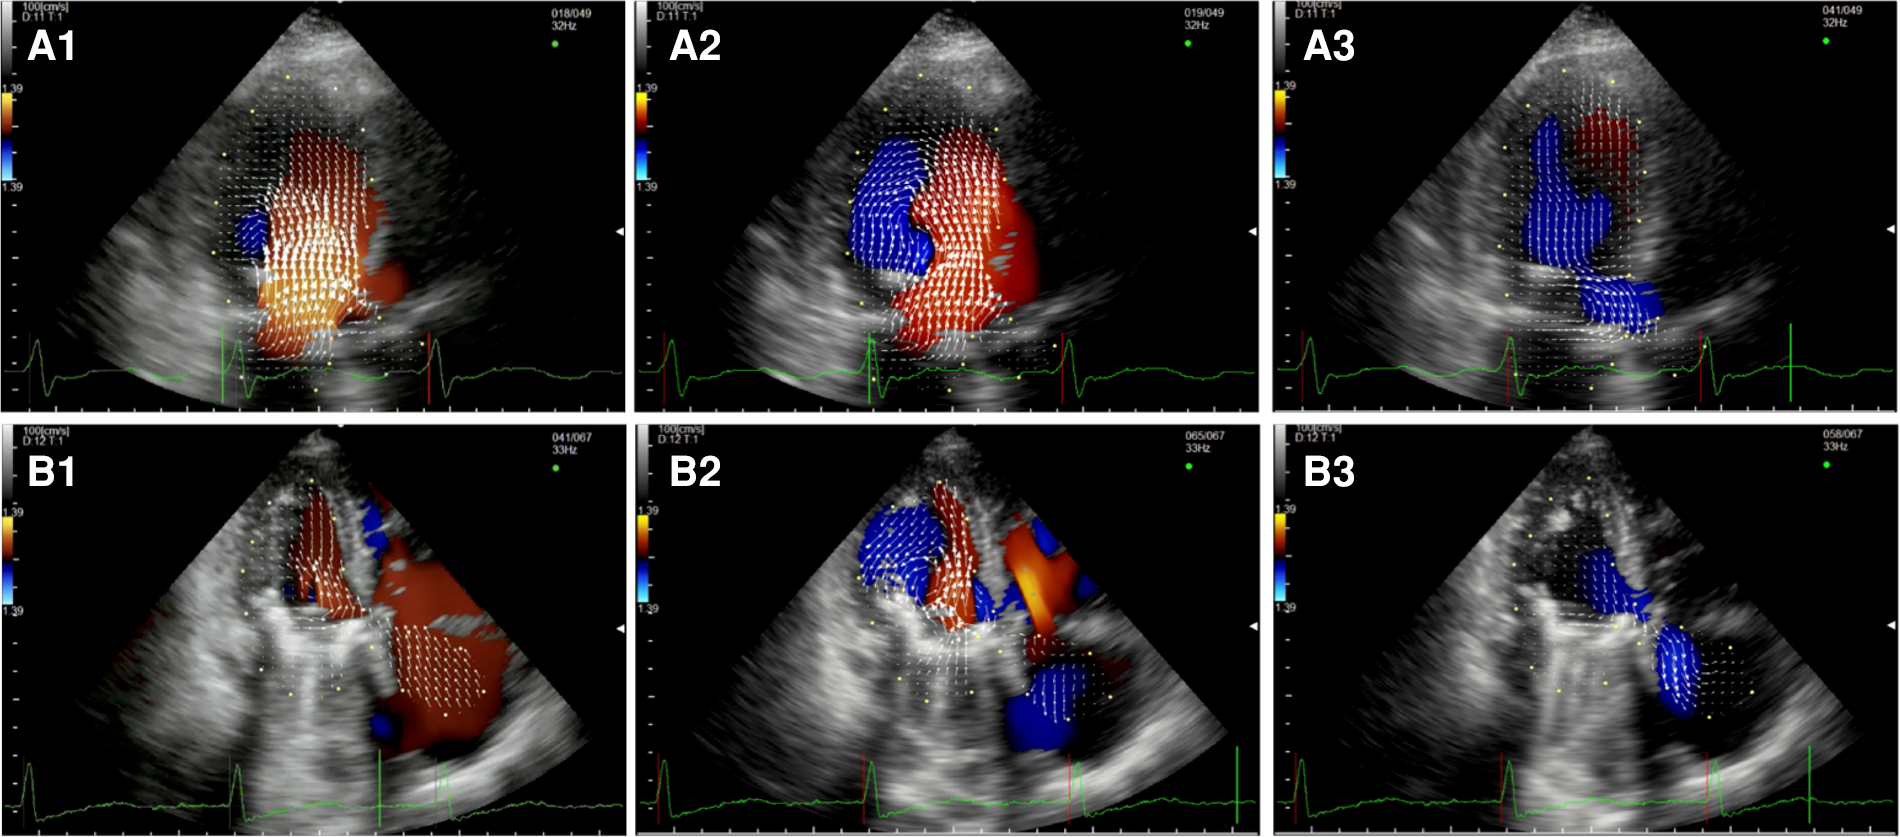

After MVRe, the intracavitary blood flow pattern is mostly restored (Figure 2, Supplementary Video S4). Whether a triangular resection alone or neochords implantation was combined with the annuloplasty ring the formation of two vortices with the movement of the blood flow toward the posterior wall of the LV could be observed, optimizing LV forces and minimizing the turbulence in the LVOT during systole. The only difference with healthy control was the slightly longer persistence of the posterior vortex during diastole.

Figure 2

Apical long-axis view. Intracardiac flow vectors in mid-to-late diastole (A1,A2) and mid-systole (A3) after surgical mitral valve repair neochords and annuloplasty ring.

After MVR with bioprostehsis (Figure 3, panel A1,A2,A3, Supplementary Video S5), we can observe in diastole only one vortex distal to the bioprosthetic valve with a counterclockwise rotation (opposite to the healthy control). The vortex occupies the center of the LV cavity to redirect blood toward the LVOT. In systole, we observed intraventricular vortices probably related to the LV systolic dysfunction. Moreover, it is possible to notice a vortex rotating clockwise within the struts of the bioprosthesis. Similarly, in patients with a mechanical prosthesis in antianatomical orientation (Figure 3, panel B1,B2,B3, Supplementary Video S6), during diastole, there is a major counterclockwise vortex in the LV mid cavity and a smaller clockwise one that disappears quickly. The main vortex redirects the flow towards the LVOT. In this group, turbulence during systole is less evident.

Figure 3

Apical long-axis view. Intracardiac flow vectors in early diastole (A1,B1) and late diastole (A2,B2) after mitral valve replacement with bioprosthesis and mechanical prosthesis (antianatomicalorientation) respectively; intracardiac flow vectors in mid-systole (A3,B3) after mitral valve replacement with bioprosthesis and mechanical prosthesis (antianatomicalorientation) respectively.